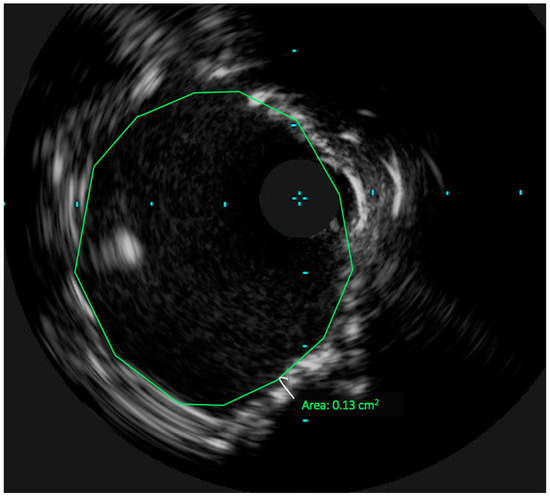

3. Technical Considerations: The Role of Intravascular Ultrasound in UPLM PCI

4. Achieving Adequate Left Main Minimal Luminal Area